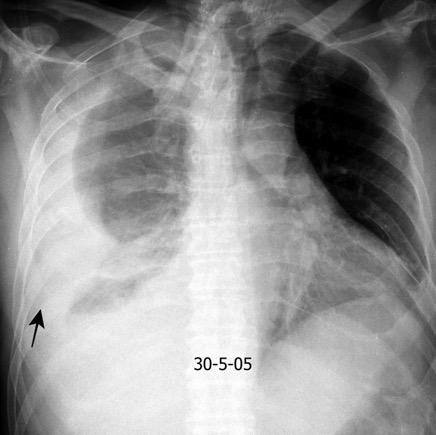

Accidente de tráfico

Rx: Niveles hidroaéreos en hemitórax izquierdo Desviación mediastínica Ausencia de intestino en abdomen. Configuración en reloj de arena del intestino herniado “Tubo nasogástrico”

Furak J et al. Diaphragm and transdiaphragmatic injuries. J Thorac Dis 2019

Recibe una puñalada en costado izquierdo

La laceración tiende a ocurrir en la unión

músculotendinosa . (64-90% en el lado izquierdo)

Diafragma “colgante” (“dangling sign”)

(“Dangling sign”)

TC. Mejor con multicorte. (reconstrucciones).

Asociación: Aire en pared.

Fracturas costal .Rotura esplénica. Neumoperitoneo.

Diafragma discontinúo Herniación de la grasa omental

Desser TS et al.The dangling diaphragm sign: sensitivity and comparison with existing CT signs of blunt traumatic diaphragmatic rupture. Emerg Radiol 2010